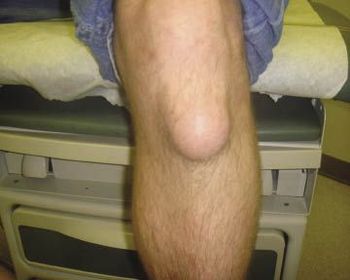

For 2 months, a 29-year-old man had pain and circular, soft swelling (7 x 7 cm in diameter) over the anterior left knee, superficial to the patellar ligament. Pain was minimal and associated with extension and flexion).